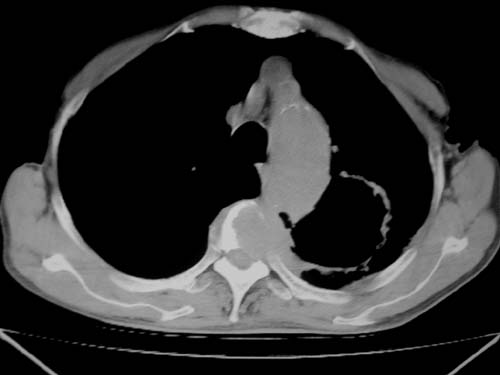

标题: CT19736:男,76岁,咳嗽,胸痛 [打印本页]

标题: CT19736:男,76岁,咳嗽,胸痛

支持左上肺周围型肺癌性并空洞形成伴胸椎转移。

左上沟癌空洞形成并胸椎转移。

考虑癌性空洞并胸椎转移。

空洞内壁有多发结节,支持癌性空洞。

左上肺癌性空洞伴胸椎转移。